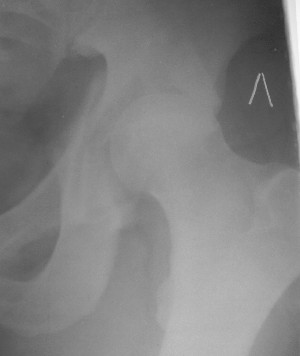

При поступлении в госпиталь 3.06.03

Больной 18 мая 2003 года в автоаварии получил перелом левой вертлужной впадины, вывих бедра. Госпитализирован в один из стационаров области.Вывих вправлен. В последствии бедро вывихивалось еще дважды. На консультацию был представлен снимок от 19.05.03г., больной переведен к нам 3.06.03г. Снимок при поступлении - перелом впадины, задне-верхний вывих бедра. 05.06.2003 г. выполнено открытое вправление вывиха левого бедра и остеосинтез стенки вертлужной впадины двумя винтами. Послеоперационный период без осложнений. Объем движений в левом тазобедренном суставе восстановился полностью. Выписан на амбулаторное лечение в удовлетворительном состоянии с рекомендациями 3 месяца ходить на костылях без нагрузки на оперированную конечность. На контрольных рентгенограммах левого тазобедренного сустава 13.10.2003 г. - признаки консолидации перелома; плотность, форма головки и состояние суставных поверхностей удовлетворительные. Разрешена дозированная осевая нагрузка, на конечность с использованием дополнительной опоры. 19.12.2003 г. больной обратился с жалобами на боли в левом тазобедренном суставе. На рентгенограммах левого тазобедренного сустава 19.12.2003 г., 20.02.04г. - асептичекий некроз головки бедра. 5.04.04г. - эндопротез. Сейчас ходит без трости, не хромает. Особенность эндопротезирования - при удалении винтов прослежена линия перелома заднего края впадины и предложено установить чашку несколько меньшего диаметра, чтобы она была покрыта несломанной частью.